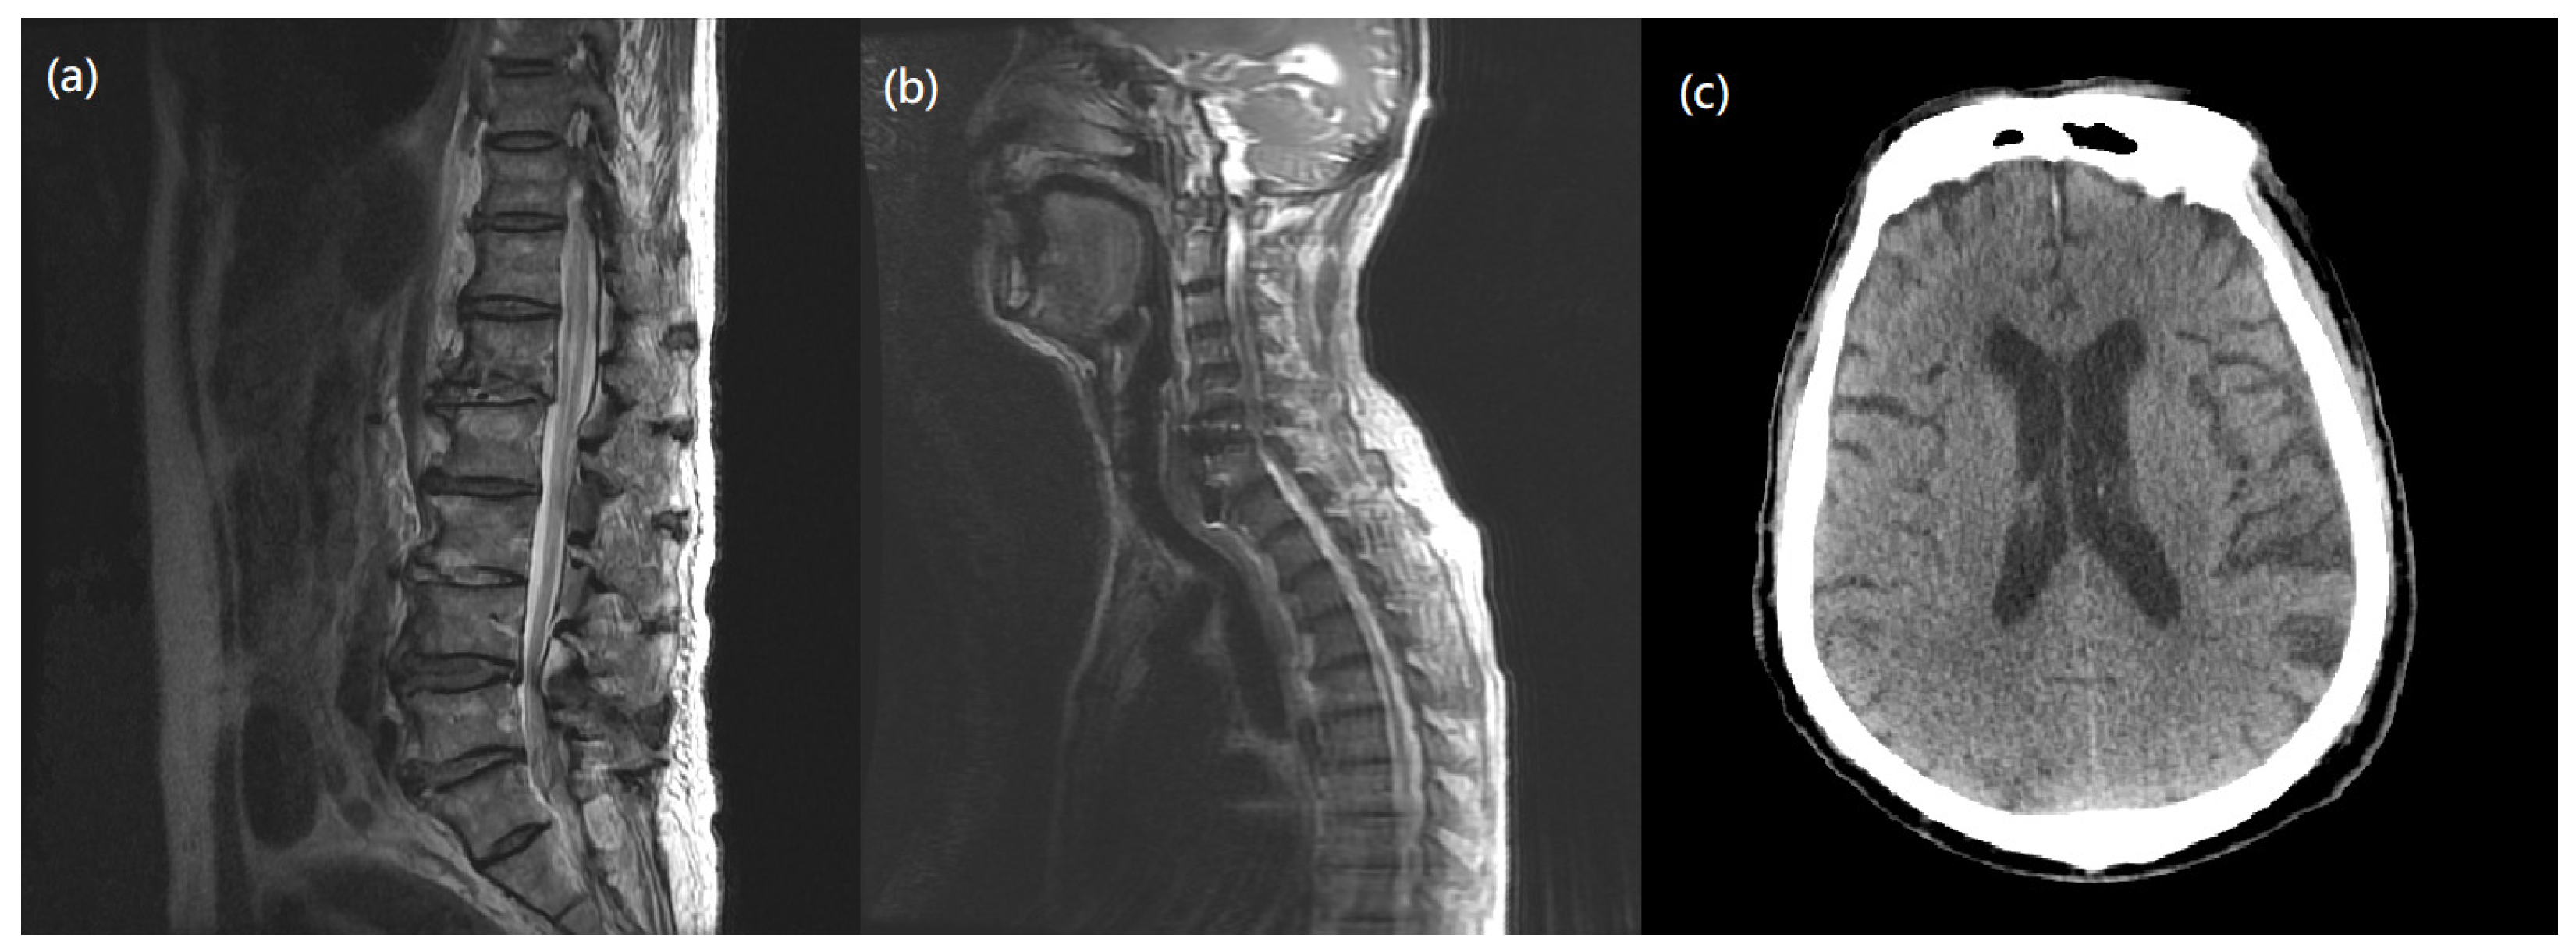

However, two weeks after surgery, his muscle strength of bilateral lower limbs suddenly diminished to grade 3/5 and continued to worsen. A neurologist was consulted to explore the causes of muscle weakness and a series of examinations were made to explore possible conditions, such as electrolyte imbalance, surgical issue of cervical spine, lumbar spine problem, or intracranial lesion. He had no medical history of a gastrointestinal tract infection or respiratory infection before or after the cervical surgery. While laboratory tests (Table S1) and microbiology studies showed unremarkable findings, ongoing infection was also excluded. Image studies (Figure 2 and Figure 3) indicated no instrumental backout, no new onset of spine stenosis, or intracerebral hemorrhage. A lumbar puncture was then performed under the suspicion of GBS. CSF studies revealed albuminocytologic dissociation, including increased protein levels (167 mg/dL) and an absence of WBC. Blood tests showed normal electrolyte balance (Table S1).

Figure 3. Postoperative Imaging. (a) MRI T2-weighted image of L spine showed L1 compression fracture, degenerative scoliosis without significant spinal stenosis or nerve root compression. (b) MRI T2-weighted image of cervical spine showed no new onset of intraspinal pathology. (c) Brain CT revealed no intracerebral hemorrhage, and no midline shift or space-occupying lesion.